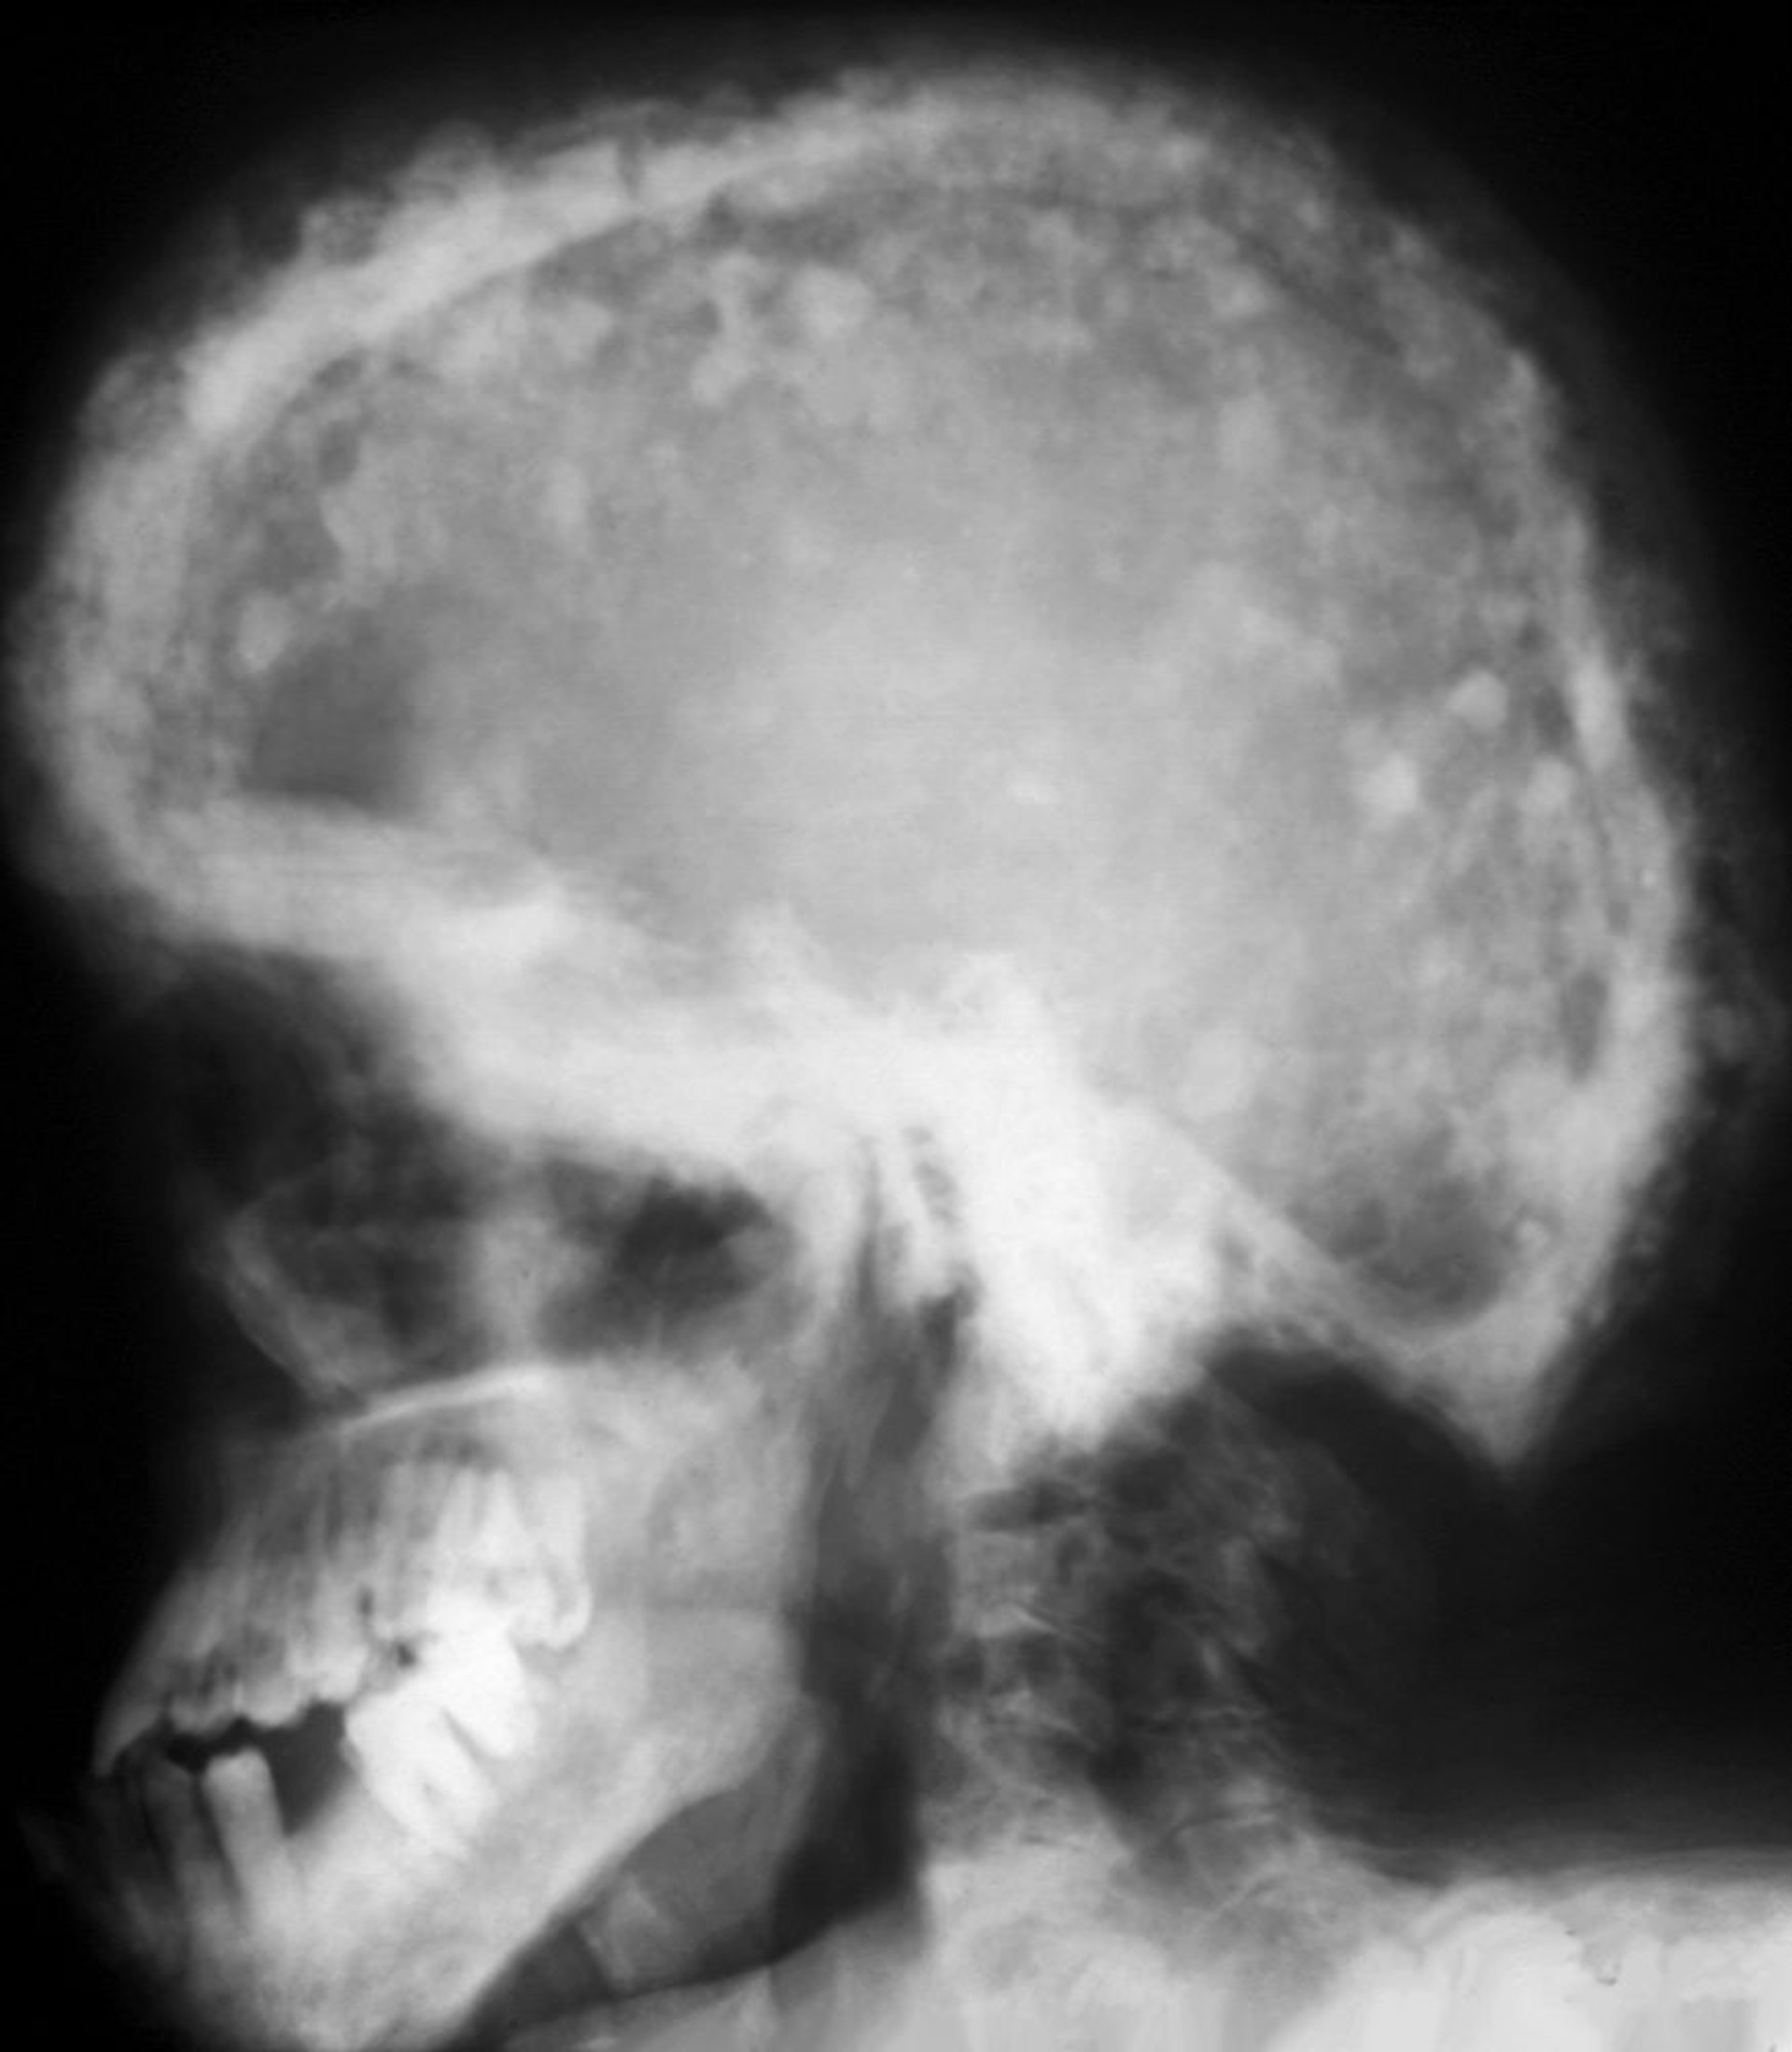

Radiografía de cráneo en la enfermedad de Paget

Patrón característico en mosaico con áreas de mayor esclerosis y radiolucidez. Estos exudados “algodonosos” se deben al engrosamiento de la bóveda craneal.